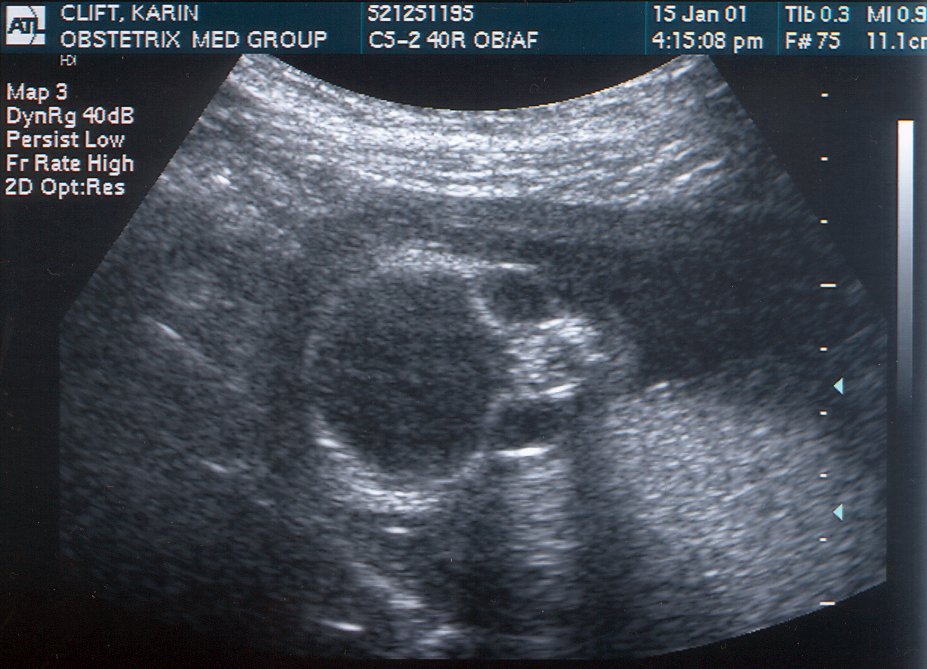

January 15 STILL looks like an alien! #1

January 3 Had trouble hearing her on the Doppler, and seeing her on the ultrasound, but we finally found out why: Rachel was doing The Twist, The Hokey-Pokey, The Monkey, and The Hustle, all rolled into one. But we finally saw her. #1